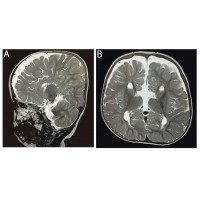

【佳学基因检测】皮层下带状灰质异位基因检测、基因解码(Subcortical band het

【佳学基因检测】皮层下带状灰质异位基因检测、基因解码(...